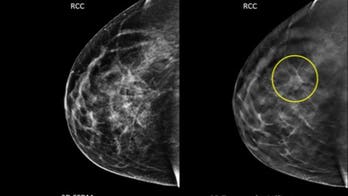

US cancer screening uneven, not up to targets In 2013, mammogram and colorectal cancer screening rates had stalled and Pap tests were on the decline, with many eligible U.S. adults not getting the recommended tests, according to a new report.